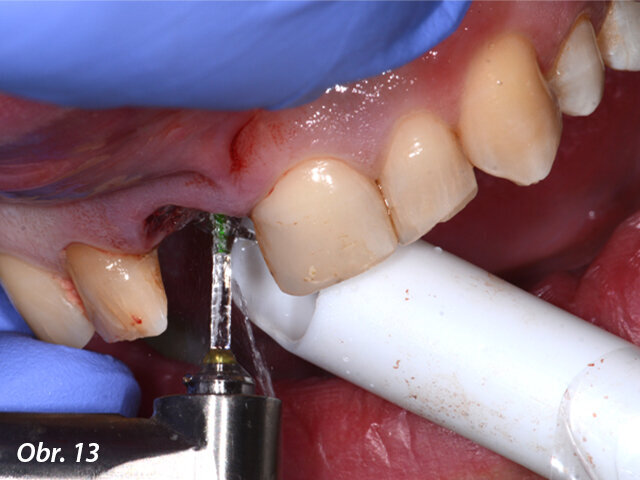

Po atraumatické extrakci zubu 11 bylo možno díky laseru Fotona LightWalker důkladně očistit lůžko zubu od zánětlivé tkáně vzniklé vlivem chronického zánětlivého stavu. Dále byla provedena dezinfekce lůžka zubu laserem Nd:YAG. Implantát byl zaveden ve správné, předem naplánované, pozici s použitím chirurgické šablony vytištěné v Belgii ze speciální lékařské pryskyřice (s možností sterilizace výrobku před výkonem). Po sejmutí šablony byla našroubována korunka spolu s abutmentem (cementováno předem mimo ústa pacienta) do implantátu a dále byla provedena fotomodelace tkání laserem Nd:YAG s cílem získání lepšího a rychlejšího hojení. Kontrolní CBCT vyšetření ukázalo ideální lokalizaci implantátu vzhledem k plánované pozici.